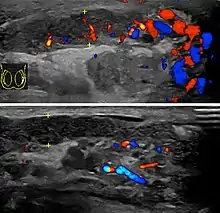

Epididymo-orchitis in a 77-year-old man. (a) Transverse sonography shows enlargement of the epididymis with hypoechogenicity noted over the testis and epididymis associated with scrotal wall thickening. (b) Color Doppler sonography showed hyperemic change of the testis and epididymis, presenting as an “inferno” vascular flow pattern.

Epididymitis and epididymo-orchitis are common causes of acute scrotal pain in adolescent boys and adults. At physical examination, they usually are palpable as tender and enlarged structures. Clinically, this disease can be differentiated from torsion of the spermatic cord by elevation of the testes above the pubic symphysis. If scrotal pain decreases, it is more likely to be due to epidiymitis rather than torsion (Prehn's sign). Most cases of epididymitis are secondary to sexually transmitted disease or retrograde bacteria infection from the urinary bladder.[4] The infection usually begins in the epididymal tail and spreads to the epididymal body and head. Approximately 20% to 40% of cases are associated with orchitis due to direct spread of infection into the testis.

At ultrasound, the findings of acute epididymitis include an enlarged hypoechoic or hyperechoic (presumably secondary to hemorrhage) epididymis [Fig. 20a]. Other signs of inflammation such as increased vascularity, reactive hydrocele, pyocele and scrotal wall thickening may also be present. Testicular involvement is confirmed by the presence of testicular enlargement and an inhomogeneous echotexture. Hypervascularity on color Doppler images [Fig. 20b] is a well-established diagnostic criterion and may be the only imaging finding of epididymo-orchitis in some men.